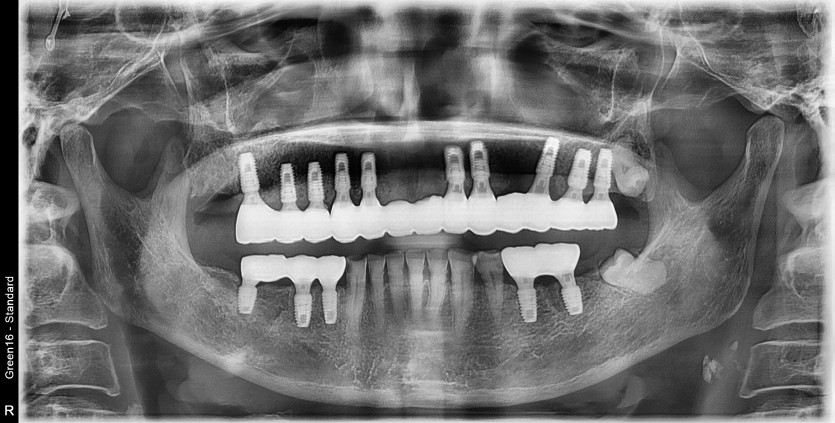

만 61세 상악 전체 임플란트 증례(하악 일부)

상악 전체 임플란트 증례입니다.(하악 일부)

15개의 임플란트로 완성하였습니다.